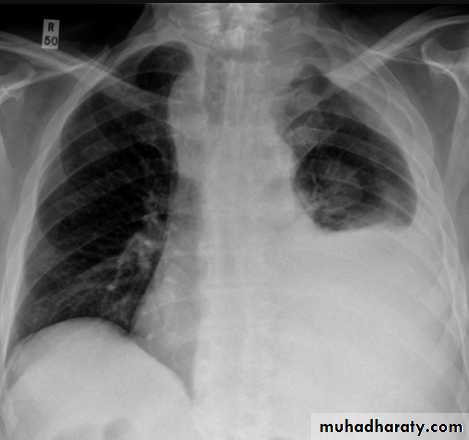

Pleural effusionPleural effusion tends to be used as a catch-all term denoting a collection of fluid within the pleural space. This can be further divided into exudates and transudates depending on the biochemical analysis of aspirated pleural fluid. Essentially it represents any pathological process which overwhelms the pleura's ability to reabsorb fluid.

Radiographic appearances

Plain radiographChest radiographs are the most commonly used examination to assess for presence of a pleural effusion, however it should be noted that on a routine erect chest x-ray as much as 250-600 ml of fluid is required before it becomes evident 6. A lateral decubitus film is most sensitive, able to identify even a small amount of fluid. At the other extreme, supine films can mask large quantities of fluid.

CXR (erect)

Both PA and AP erect films are insensitive to small amounts of fluid. Features include:

blunting of the costophrenic angle

blunting of the cardiophrenic angle

fluid within the horizontal or oblique fissures

eventually a meniscus will be seen, on frontal films seen laterally and gently sloping medially (note:

A subpulmonic effusion (infrapulmonary effusion) may be seen when there is previously established pulmonary disease, but can also be encountered in normal lungs , They are more common on the right, and usually unilateral

with large volume effusions, mediastinal shift occurs away from the effusion (note: if coexistent collapse dominates then mediastinal shift may occur towards the effusion)